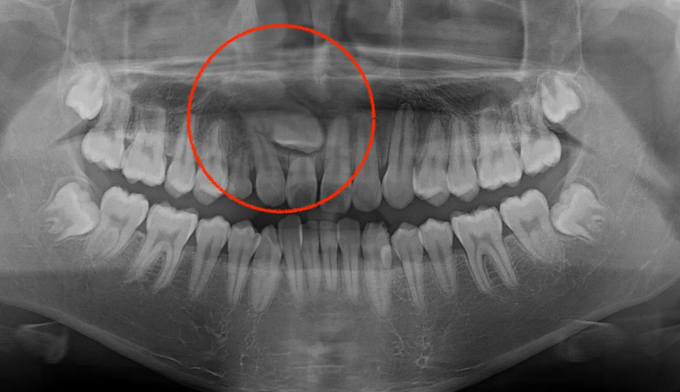

송곳니가 원래 나와야할 방향 말고 앞니쪽으로 나온 케이스입니다.

벌써 멀쩡한 영구치 앞니의 뿌리를 모두 녹여버렸습니다.

어쩔수 없이 뿌리가 녹은 앞니를 발치하고 해당위치로 송곳니를 맹출시켰습니다.